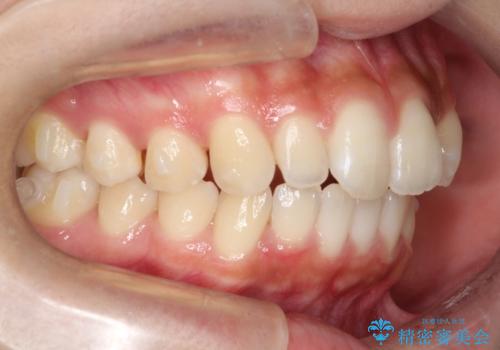

- 前歯の歯並びの改善を希望され来院された患者様です。

初診時の歯並びの状態としては、上下ともに全体に及ぶの中等度のがたつき(叢生)があり、全特に左上の前歯は1本だけ引っ込んでいる状態でした。

抜歯は行わず上顎の奥のスペースを利用して歯をスライドする方法の他に歯列弓の拡大やディスキング(歯と歯の間の隙間を作る処置)を行い叢生を改善しました。

歯の大きさの不揃いが原因の正中のズレは、ディスキング量を調整することで合わせています。

上の歯を後ろに送る方法として、歯茎に入れた小さなネジからゴムかけをして歯列全体を後ろに引っ張りました。